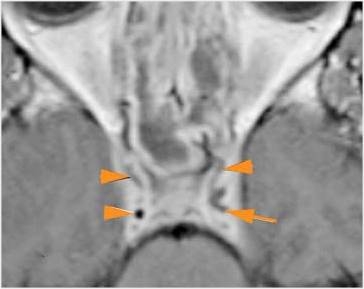

There is a subperiosteal fluid collection or abscess along the boney walls of the anterior or middle cranial fossa. |

Yes | NA |

There is an epidural fluid collection or abscess along the boney walls of the anterior or middle cranial fossa. |

There is brain edema specifically involving the frontal and temporal lobes. |

There is cerebritis specifically involving the frontal and temporal lobes. |

Findings are consistent with the clinical diagnosis of acute or subacute sinusitis superimposed on chronic mucocele with intracranial complications of epidural empyema along the orbital roof and early frontal lobe cerebritis.